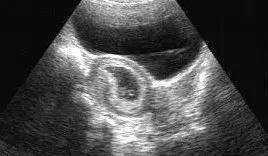

B超就是利用超声波了解体内结构的一种观察仪器。原理说白了很简单,就是发射超声波,超声波也是声音的一种,具有穿透能力,并且和所有的声音一样,遇到屏障会产生回声,不同的屏障回声的方式也不同,于是利用电脑收集这些回声,转化为相应的图像在屏幕上显示出来,起到观察内部脏器等作用。

彩超和B超的主要区别可不是像彩电和黑白电视机那样简单。彩超的主要技术指标如(探头晶片数、成像通道数、成像动态范围、主机处理能力和深度等方面)均大大高于B超。

因此能够显著提高图像分辨率,可以更早期发现更细小的病变,提高疾病的早期诊断率,并可更清晰地显示病灶周边和内部变化的细节,提高诊断的准确性。

彩超具有彩色多普勒血流显像功能,可以显示病变区域的血管解剖结构、血流方向、血流速度和血流状态改变,可以明显提高对疾病的鉴别能力,提高诊断的准确性。

彩超具有策划谐波成像功能,可以明显降低因肥胖、气体和其它伪像干扰,提高图像清晰度。因此,彩超检查能够更早期地发现病变,并能够更加准确地对病变进行鉴别诊断,明显提高诊断的准确率,而B超检查的漏诊率和误诊率则明显高于彩超。